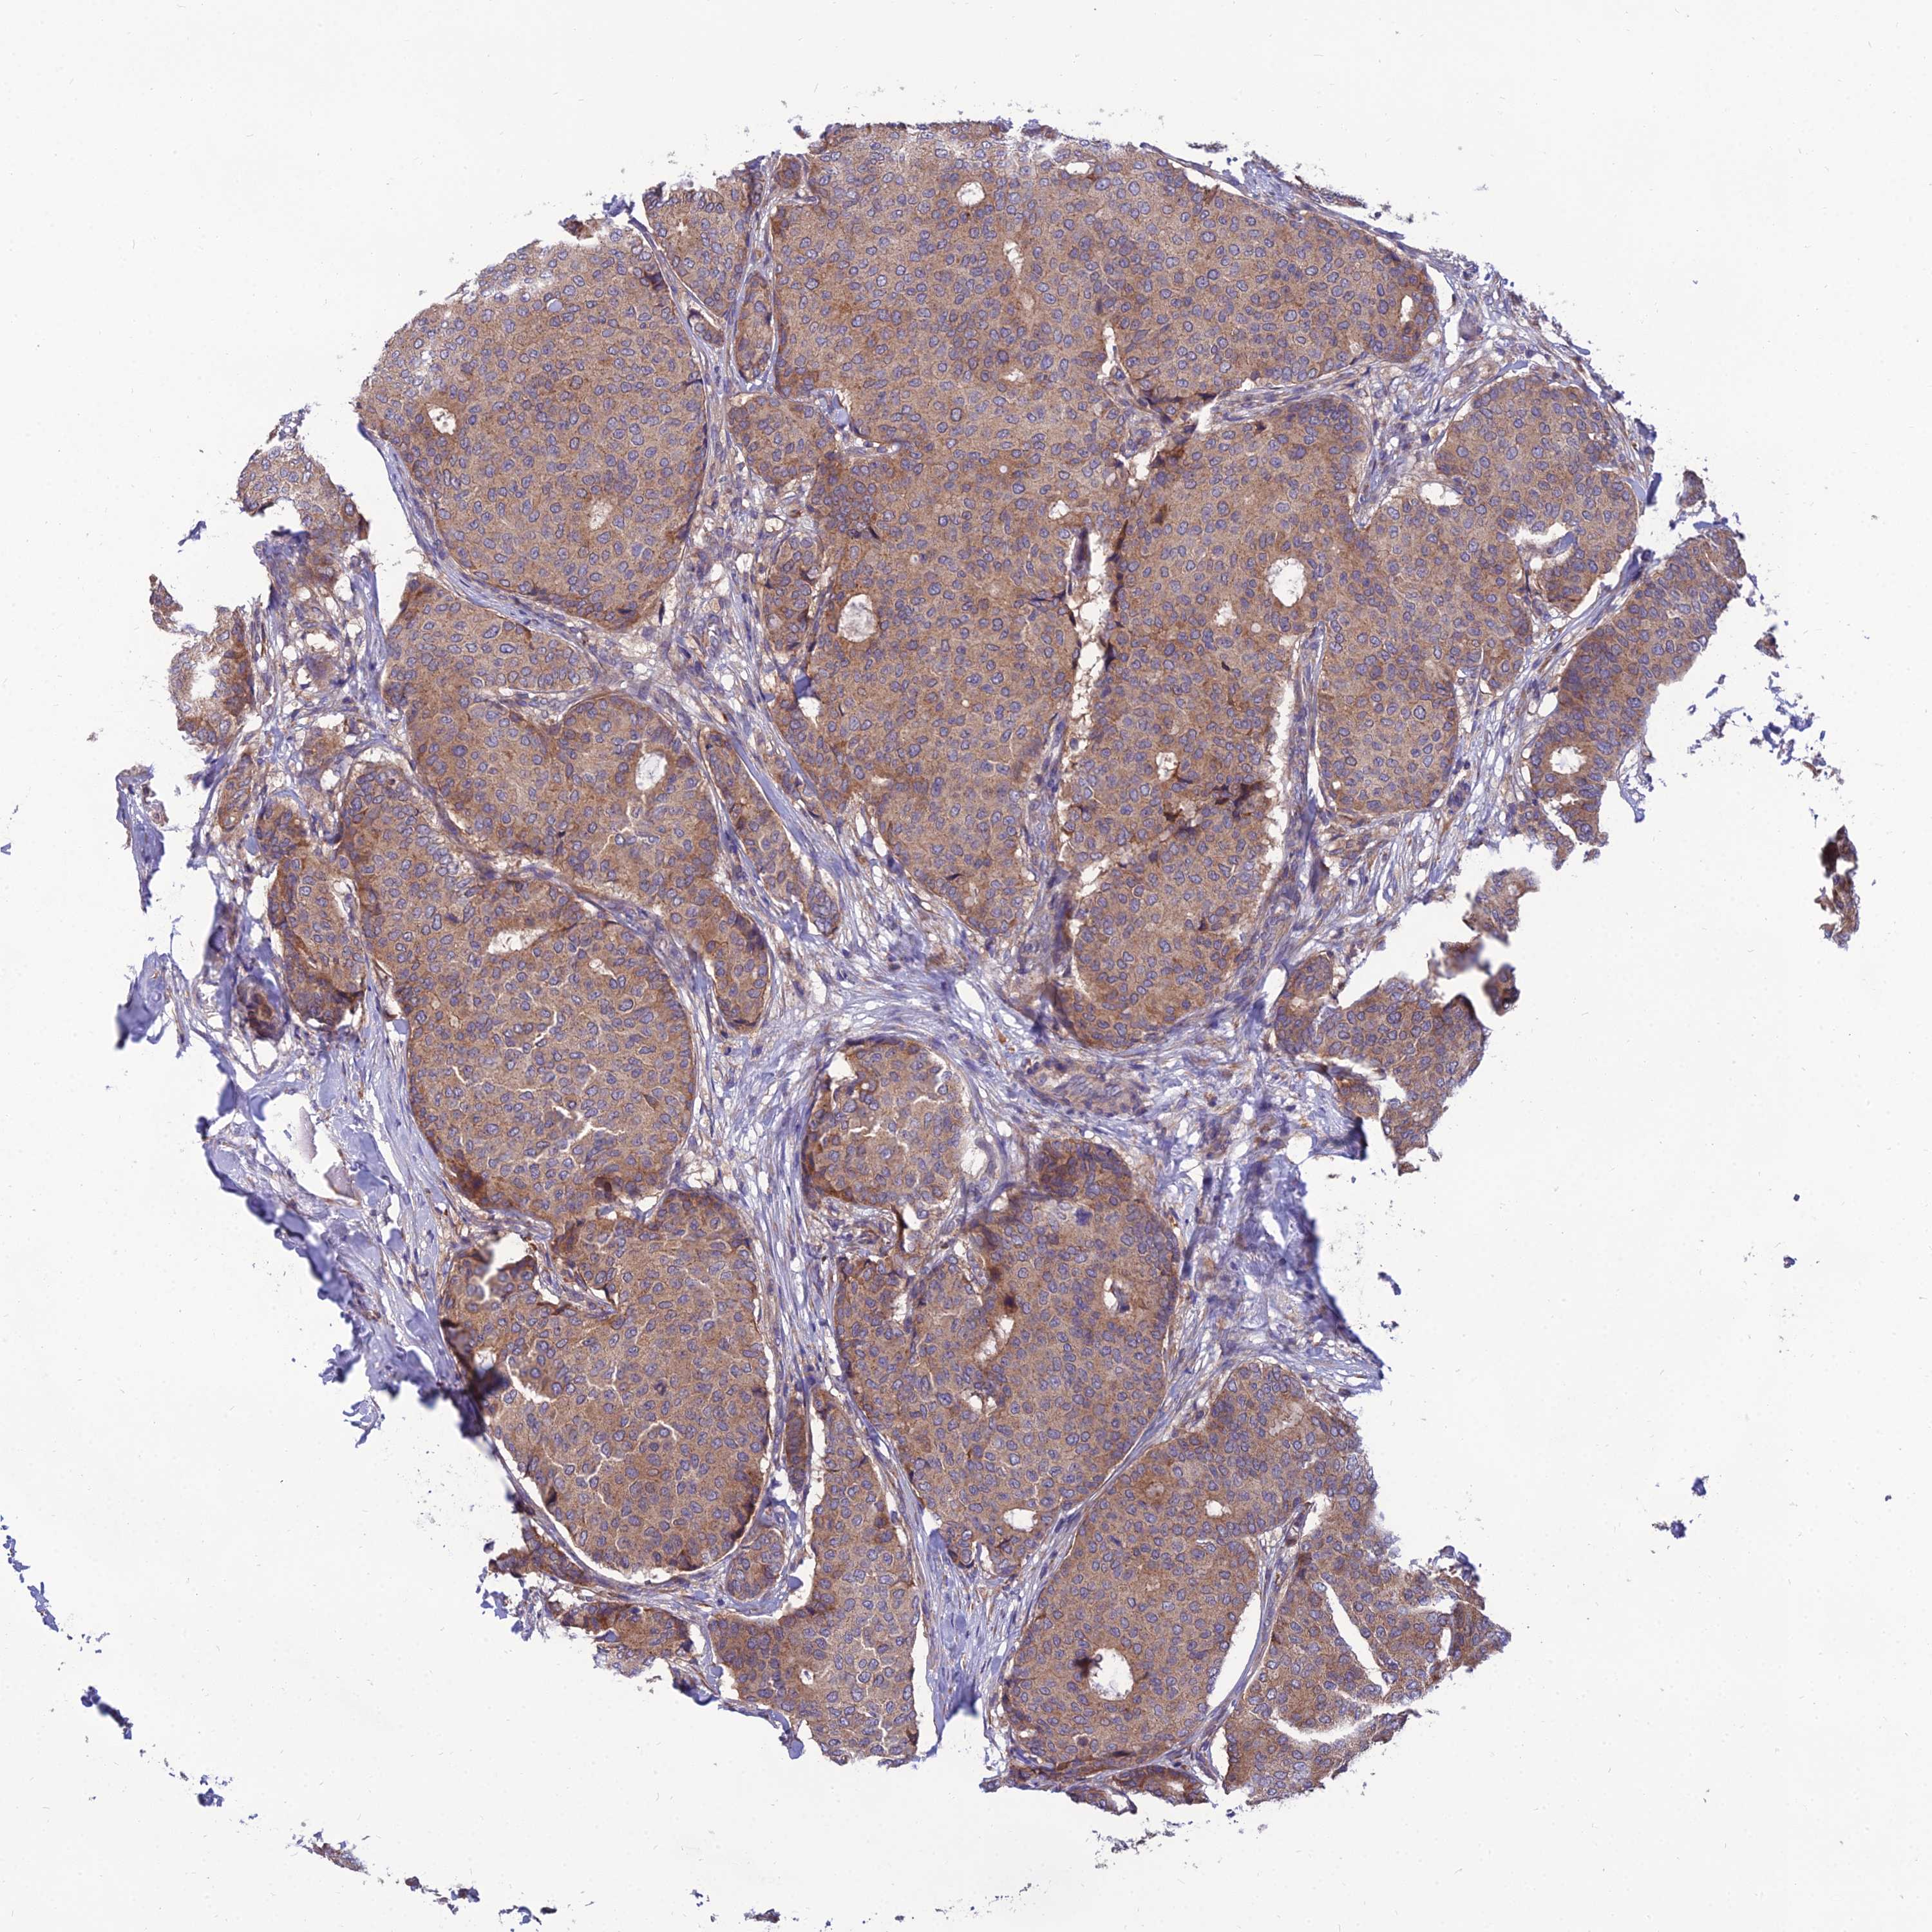

BRCA TCGA BRCA VALIDATION PROTEIN EXPRESSION

ANTIBODIES

AND

VALIDATION